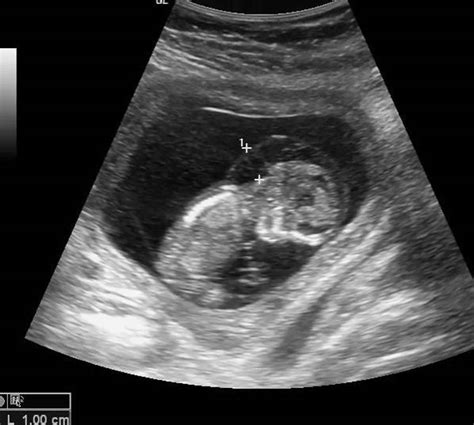

• Abnormal Ultrasound Findings: Ultrasound examinations may reveal fluid accumulation in the fetal tissues or body cavities.

• Ultrasound: Ultrasound examinations are the most common method for detecting fetal edema. They can reveal fluid accumulation in the fetal tissues and body cavities.